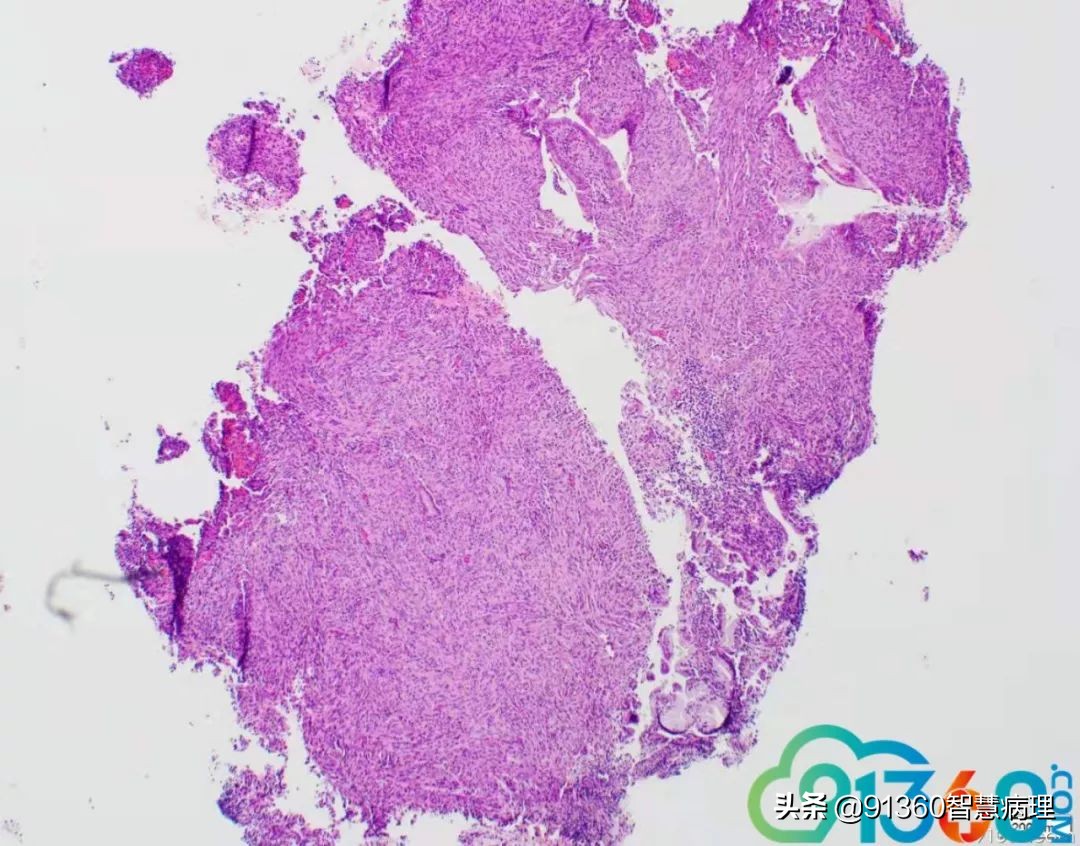

邢德印 39岁,宫颈活检 石岩 腺肉? 任永昌 梭形细胞恶性肿瘤,肉瘤首考,肉瘤样癌次之! 郭晓静 @邢德印(妇科病理)邢老师, 周末好!您的病例肯定有难度谢谢分享!抛砖引玉,我说下自己看法。1.39岁,为什么要活检?hpv情况和液基肯定有问题2.低倍这一点给我的感觉是有异型,其他很多似乎很弥漫,没有找到鳞状上皮,梭形细胞样

郭晓静 3.粘液上皮并没有小叶状结构,分散零散,最左边也就是放大倍数的 我感觉是有异型性的4.所以,是鳞的病变还是腺的病变,还是合并?还是梭形细胞间叶源性的病变~~我没有把握 但腺肉瘤的话,我感觉是不是要看到低倍的袖套样结构呢? 期待老师讲解!谢谢分享!